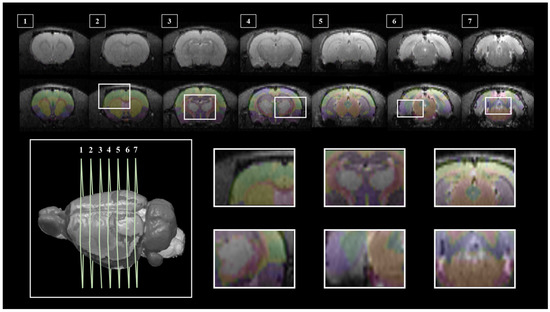

3.1. SIGMA Atlas-Based Whole Brain Segmentation and Registration